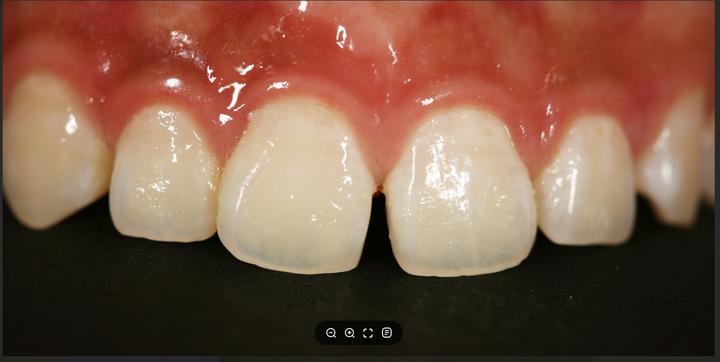

ハル歯科医院は、最先端のインプラント歯科治療に特化したクリニックです。代表のジョー・ハング院長は日本の神奈川歯科大学を卒業し、両国での歯科医師免許を保持。さらに、韓国で専門医資格を取得し、口腔外科など高度な手術経験も豊富です。すべての治療を院長自らが行う専任診療制を採用しており、流暢な日本語で対応可能。「デジタルインプラント」や「無削除ラミネート」などの最新のデジタル歯科治療を、日本の約半額で受けられます。仁川・金浦空港から乗り換えなしで行ける孔徳(コンドッ)駅すぐとアクセスも良好で、旅行者にも便利な立地となっています。